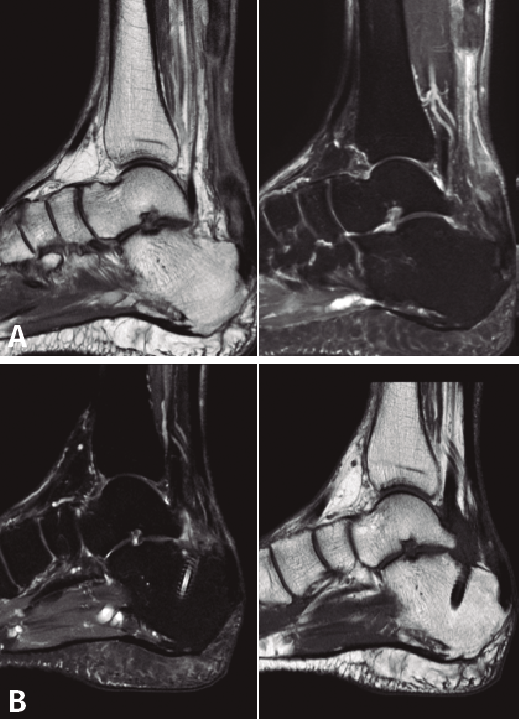

Posteriormente, a todos pacientes se les realizó una RM postoperatoria a los 9-12 meses, para observar la correcta integración de la plastia en el túnel del calcáneo. En todos los casos se objetivó la reparación del defecto del TC, lo cual lo atribuimos a la aposición del vientre muscular del FHL y a la carga en ausencia de estrés mecánico (Figura 5).

Figura 5. Imagen de resonancia magnética (RM) preoperatoria (A) y RM a las 16 semanas postoperatorias (B), donde se observa la correcta integración de la plastia en el túnel del calcáneo y la reparación e hipertrofia del tendón calcáneo.